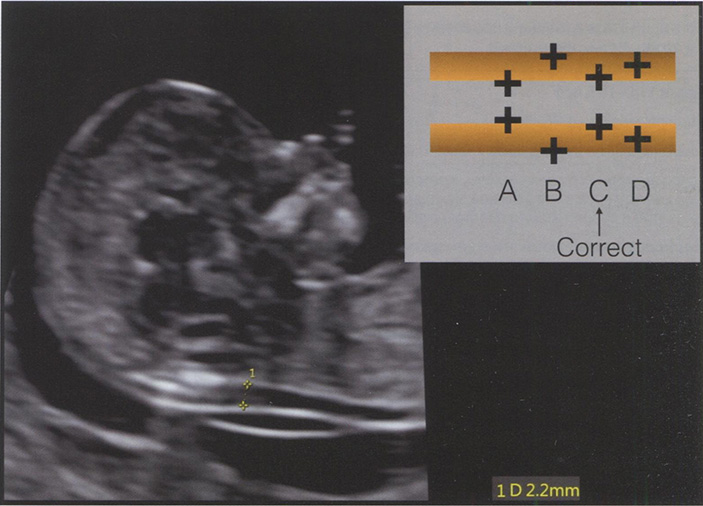

Воротниковое пространство - это ультразвуковое изображение скопления жидкости под кожей в области задней поверхности шеи плода в I триместре беременности. Правильная подготовка специалистов, проводящих ультразвуковое исследование, и строгое соблюдение установленных единых методических рекомендаций по ультразвуковой оценке ТВП лежат в основе точного (то есть с минимальным разбросом показателей) измерения этого параметра разными операторами. Получение качественного ультразвукового изображения в определенной плоскости способствует повышению точности измерения ТВП (рис. 1.1). С целью уменьшения погрешностей, возникающих при работе разных специалистов, некоторые производители ультразвукового оборудования предлагают полуавтоматический метод оценки ТВП (рис. 1.2). В табл. 1.1 приведены все существующие на сегодняшний день критерии правильного измерения ТВП. Роль оценки ТВП в выявлении анеуплоидий обсуждается в главе 6.

Рис. 1.1. Ультразвуковое изображение среднесагиттального среза головы плода в 13 нед беременности, демонстрирующее измерение ТВП в соответствии с рекомендованными стандартами (см. табл. 1.1 и 1.7). Схематическое изображение правильного (Correct, С) и неправильного (А, В, D) расположения калиперов при измерении ТВП. В данном случае ТВП составляет 2,2 мм.